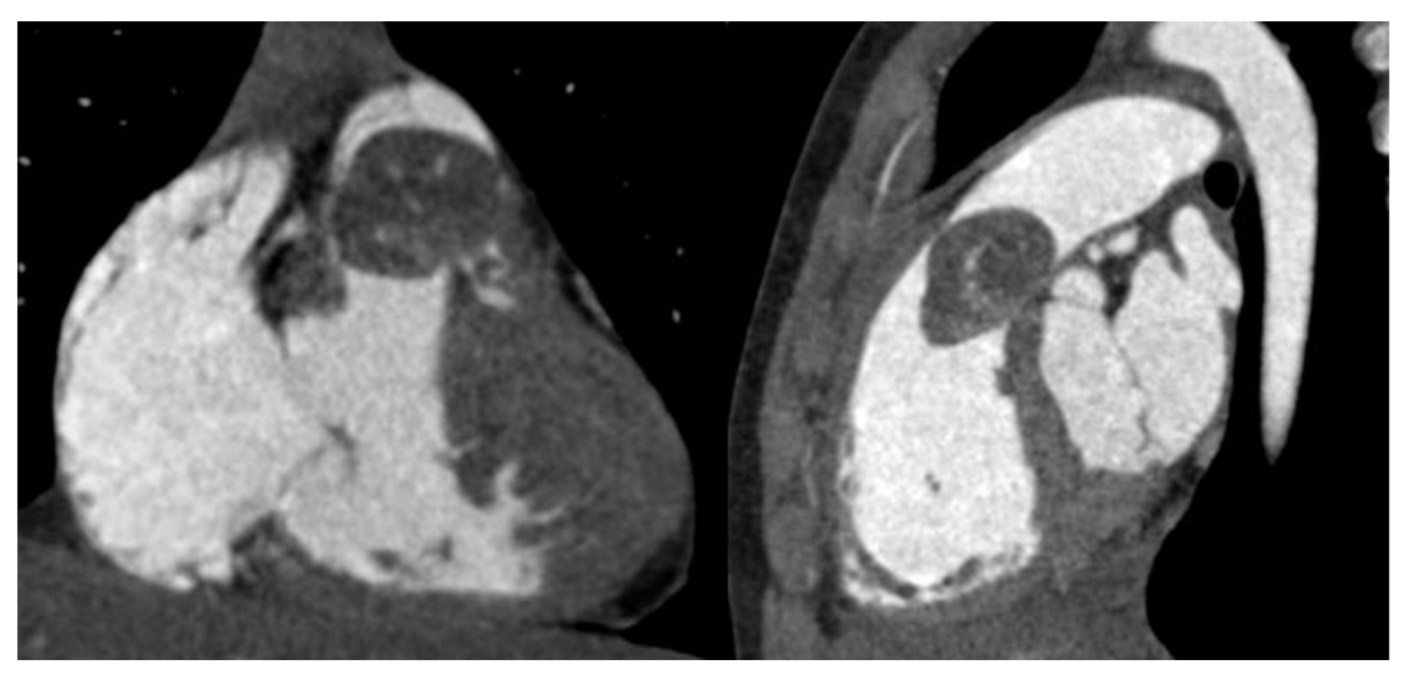

Echocardiogram identified a rounded and lobulated voluminous (3.5 × 4 cm) mass with clear margins and inhomogeneous content, adherent to the infundibular septum through a pedicle. The right ventricle outflow tract (RVOT) showed a severe obstruction with a maximum instantaneous systolic gradient of 80 mmHg, sparing the pulmonary valve (Figure 2 and Figure 3). The right atrium (Area 23.5 cm2) and ventricle (tele-diastolic area was 23 cm2 and tele-systolic 19 cm2) were dilated with a severe systolic dysfunction (Fractional Area Change of 18.6%).

Transthoracic echocardiography shows the presence of a mobile intracardiac mass protruding into the right outflow, attached to the infundibular septum by a peduncle.